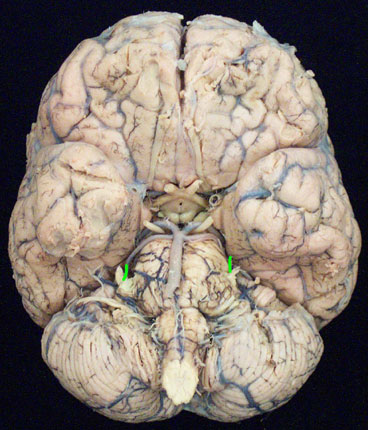

FUNCTION: motor to the superior oblique extraocular muscle The trochlear nerve passes through the SUPERIOR ORBITAL FISSURE where it supplies the superior oblique muscle of the eye. Injury to this nerve inhibits the eyeball from turning out and down (inferolaterally). This is seen clinically as DIPLOPIA (double vision). CN IV is the only cranial nerve to emerge dorsally from the brainstem. |